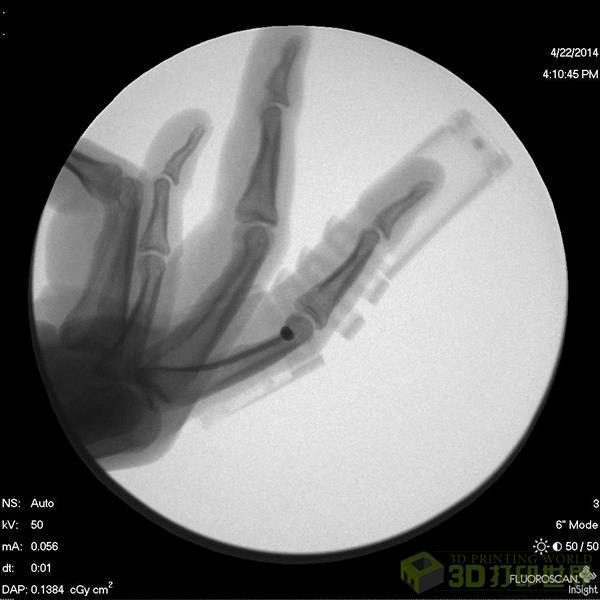

近日,来自新加坡国立大学及其附属医院的研究团队开发出一种3D打印的可弯曲指夹板,可以用来固定受伤的手指部位,同时允许手指做出一些简单的活动,促进关节愈合。

这种3D打印的指板夹提供了一张更为有效、符合人体动态牵引机制的方案。“这种器械装置使用简单、外观时尚简洁,比一些常用的医疗方案在价格方面更为实惠。”弹簧式的结构,能够将手指固定在适合连接愈合的位置,同时一定程度上活动恢复。一般来说,患者只需正确佩戴4-6周就能痊愈。

这个指板夹包括5个部分:支撑底座、夹板、帽端、连接旋钉、线。3D打印实现了指板夹的个性化定制,可以利用已有的医疗扫描数据,与每个佩戴者进行精确匹配。手术时甚至不用针切口,大大降低感染率。